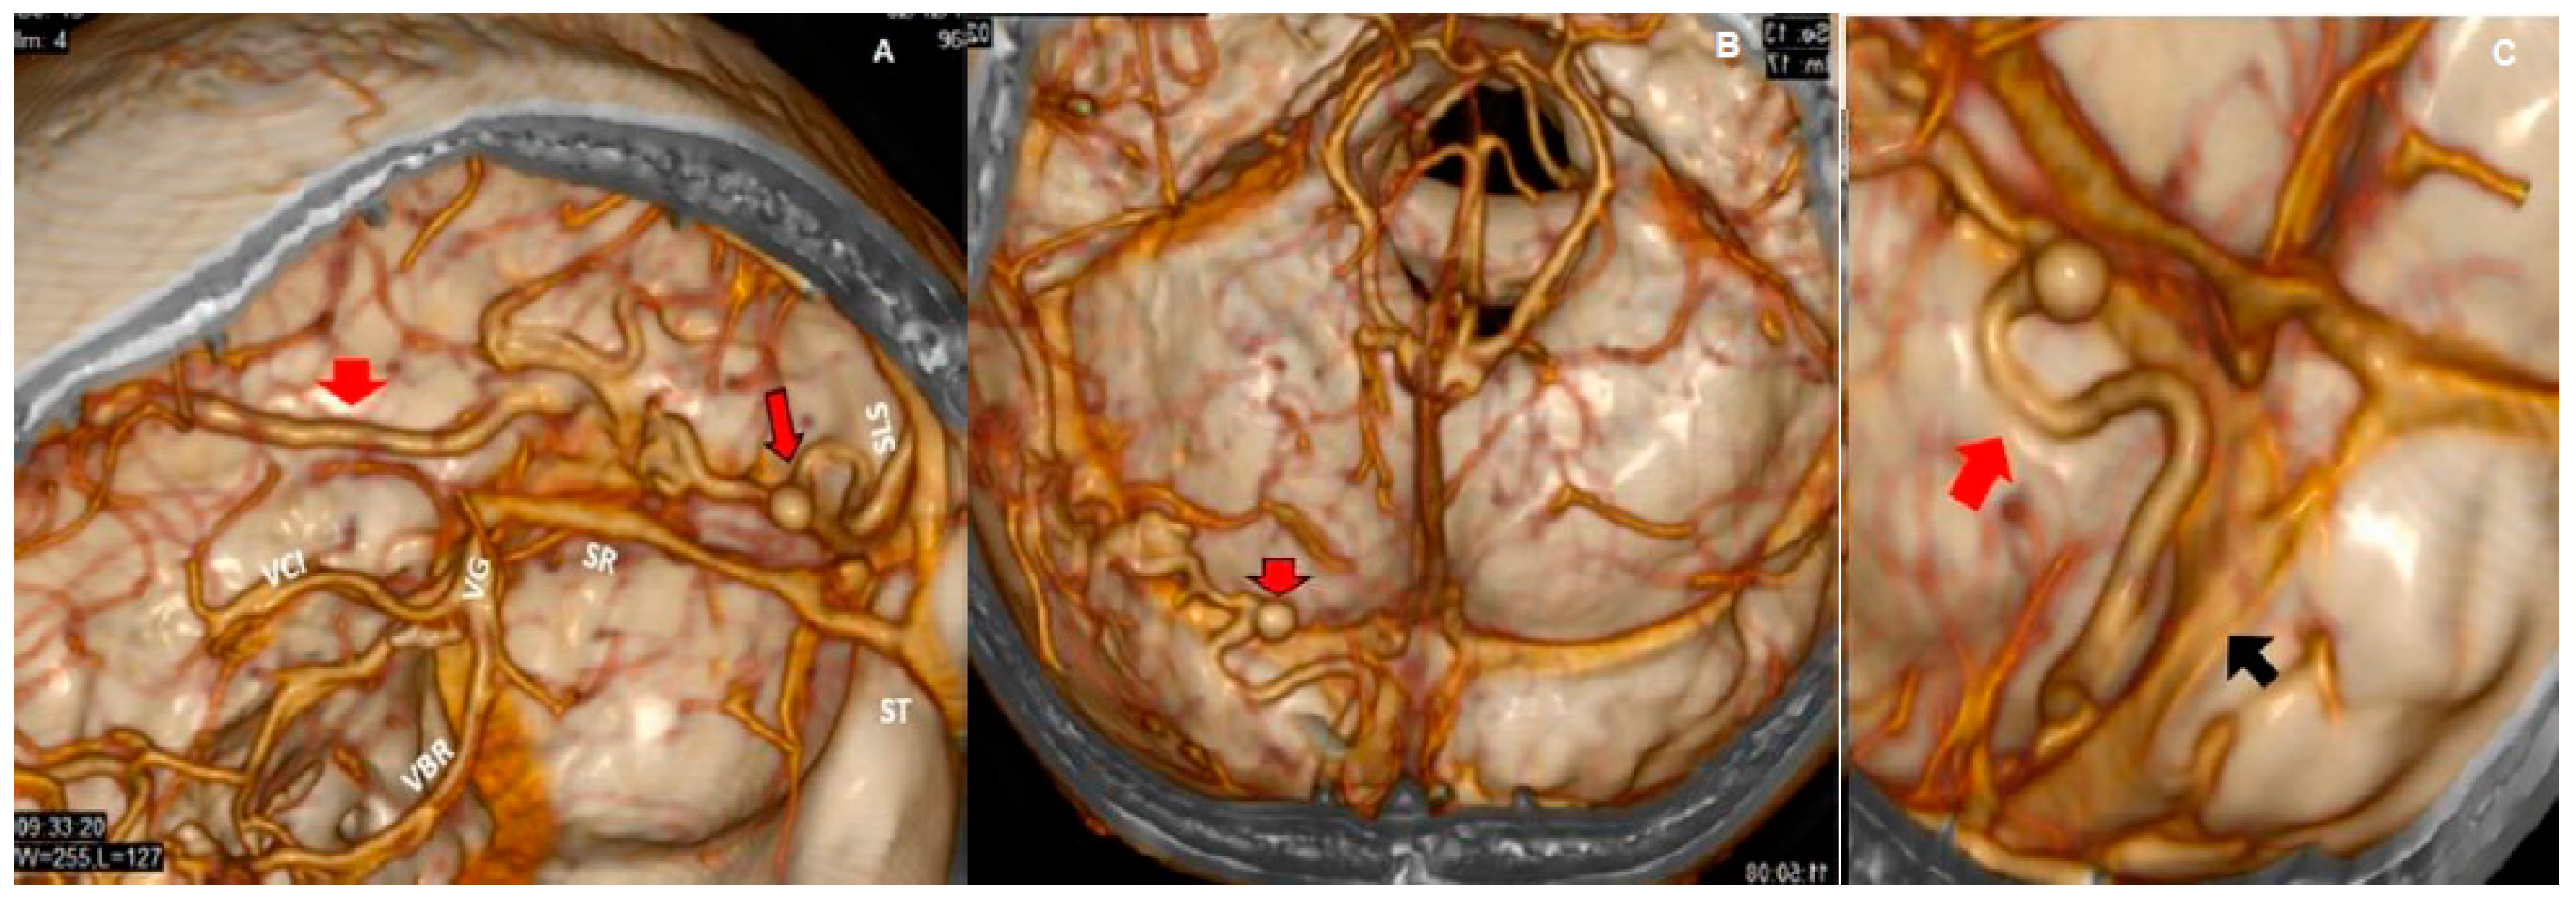

Both hematomas were reabsorbed gradually (Figure 2), with satisfactory clinical evolution after a two-month follow-up period. Figure 2 shows the increased frontal subdural hematoma and its extension to parietal and frontal lobes. Angiography revealed ecstatic cortical veins, one of them with saccular dilatation adjacent to the IPH (Figure 3). For this reason, we decided to perform cerebral angiography, which confirmed the dural arteriovenous fistula. It connected the artery, a branch of the external carotid artery, with cortical veins in the superior sagittal sinus drainage (Figure 4). After endovascular therapy, the evolution of the patient was satisfactory (Figure 5 and Figure 6). Two years later, no bleeding had appeared, and the subsequent angiographic studies were negative.

Figure 4.

3D CT reconstructions of vessels and sinus (A–C). The saccular dilatation (red arrows with black borders in A,B) and drainage veins (red arrows in A and C) go toward the superior longitudinal sinus; the transverse sinuses are permeable. The upper longitudinal sinus (SLS, black arrow in C) at the level of the Herophilus prensa is fenestrated by arachnoid granulations or partial thrombosis that narrow it. The internal cerebral veins (VCI), basal veins of Rosenthal (VBR), vein of Galen (VG), rectum sinus (SR), and transverse sinuses (ST) all have a normal caliber.